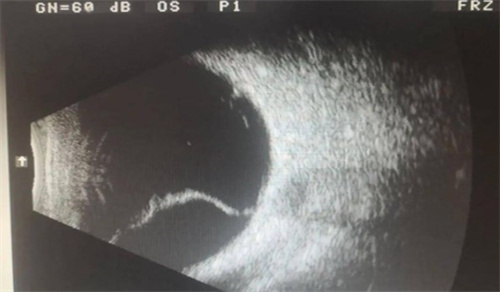

视网膜脱离手术后多长时间内做网脱手术?

视网膜脱离手术的佳时间取决于脱离范围、类型以及病情进展:

早期脱离(黄斑未脱):在1-2周内进行手术结果佳,能显著提高视力复原结果。

黄斑脱离或病情重度:需在48小时内紧急手术,以减少长久性视力损伤风险。

牵拉性视网膜脱落:手术时间会根据病情稳定情况制定。

若延误治疗,视力复原结果会明显下降,甚至无法复原正常视觉功能。